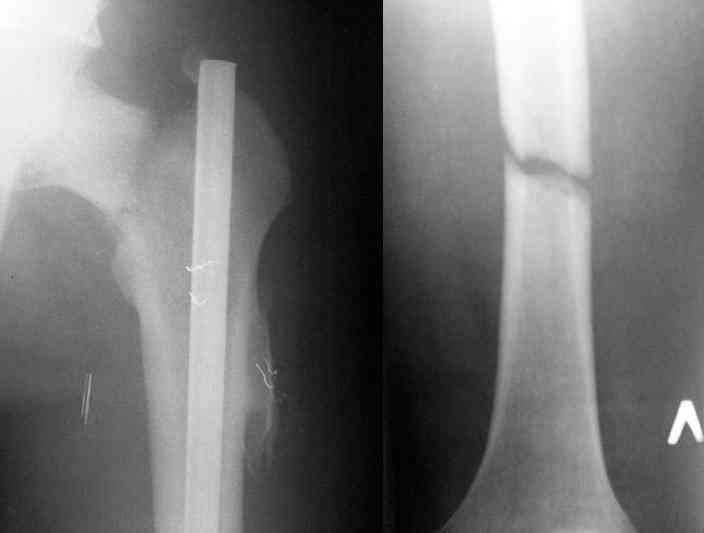

Здесь представлены снимки больного 65 лет, поступившего с диагнозом перелом

бедра после автоаварии.

В первый же день произведено антеградное штифтованием DePuy Trochanteric Nail.

На второй день (7) обнаружен пропущенный перелом,

и проведены шурурпы через и спереди штифта без удаления.

Послеоперационные снимки